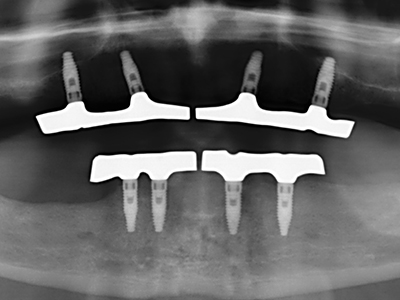

Indication: Bone splitting

Bone tissue is not simply a mineral structure but also contains a substantial proportion of collagen fibres. This means it not only has good compressive strength but also a degree of flexibility, which can be taken advantage of when performing bone augmentations. In the classical expansion procedure using bone splitting, the atrophied alveolar ridge is split longitudinally and carefully expanded after reaching an adequate osteotomy depth (Fig. 13-16), ideally without substantial removal of the periosteum (Brugnami, Caiazzo et al. 2014, Stricker, Fleiner et al. 2014). Screw and plate systems with increasing expansion distance have proven effective in separating the two bone lamellae while remaining below the fracture threshold. In general, residual bone widths of at least 3–4 mm are required (Chiapasco, Zaniboni et al. 2006) to guarantee adequate flexibility and sufficient bone coverage of the future implants. If necessary, a vertical relief osteotomy on one or both sides can improve flexibility. A combination with additional augmentation techniques, particularly on the buccal side, has been described as an alternative to the classical technique.

The splitting procedure is particularly atraumatic and there is no significant loss of dimension when using piezosaws, and there are no significant differences between implants in split jaws and implants in an alveolar ridge without a bone deficit (Chiapasco, Zaniboni et al. 2006, Danza, Guidi et al. 2009). However, sufficient continuous irrigation is essential, particularly with locally restricted and deep splitting to prevent thermal stress in the apical osteotomy regions.